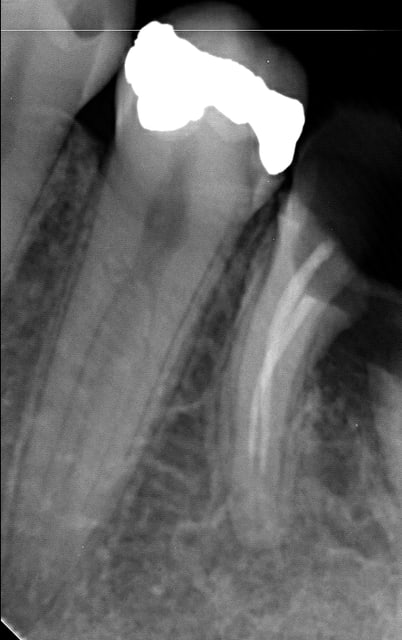

27/02/2014 à 20h41

Celle de ce soir :

Par contre j'ai souvent des douleurs importantes lors de l'alésage sur les dents de ce type : longues à racines fines. Je ne comprends pas malgré l'intrapulpaire, les patients ont parfois super mal. SI quelqu'un sait ce qui peut être en cause?

Endo 11  1  preop iisxij - Eugenol

Endo 11  2  fin r8k5a2 - Eugenol